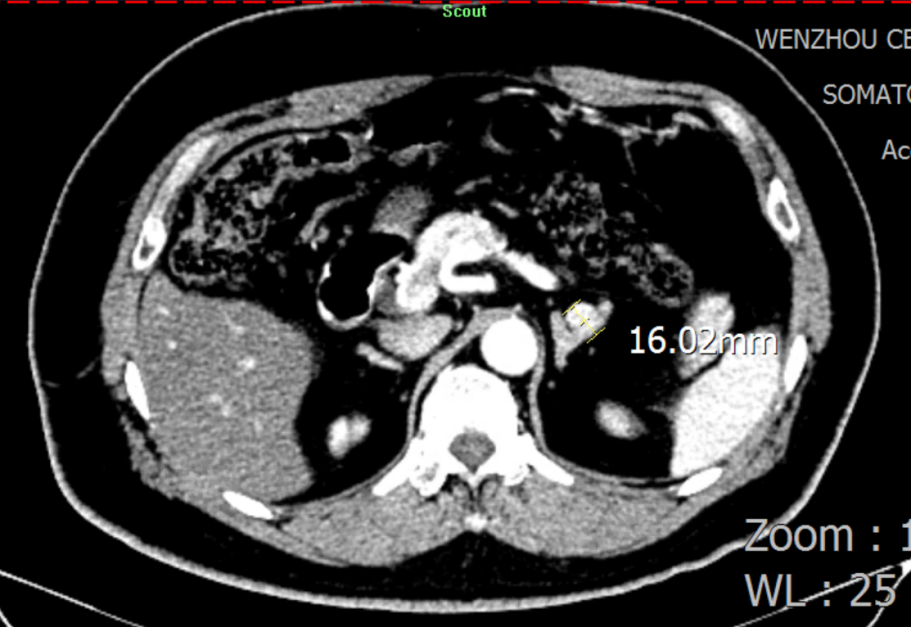

二十年前被诊断为高血压 血压控制不睬想引发两次脑出血 高峻爷的病史要从二十年前提及。。。。。。2003年,,,,,,,,在一次体检中被发明血压升高抵达150/100mmHg,,,,,,,,经外地医院诊断为高血压,,,,,,,,时值壮年的高先生没有太在意。。。。。。 然而,,,,,,,,让人没想到的是,,,,,,,,2011年,,,,,,,,在完成一次高负荷的事情后,,,,,,,,高先生马上感应天旋地转,,,,,,,,再度醒来时已经接受了小脑血肿扫除和去骨瓣减压术。。。。。。 “幸亏救护车来得实时,,,,,,,,我的命是脑外科医生从死神手里夺回来的。。。。。。”之后,,,,,,,,高先生提前过上了退休生涯,,,,,,,,只管遵医嘱准时服用降压药,,,,,,,,但血压控制并不睬想,,,,,,,,还被诊断为重度壅闭性睡眠呼吸障碍综合征,,,,,,,,使得血压控制更难了。。。。。。 2019年,,,,,,,,149/85mmHg的血压再次向他的血管提倡攻击,,,,,,,,高先生因右侧小脑血肿再次入院。。。。。。这对刚刚脱离手杖的高先生而言,,,,,,,,又是一次重大攻击。。。。。。 二十年后经精准诊断 行左侧肾上腺切除术后病情显著改善 心肌标记物、肝肾功效、血糖、血脂、甲状腺功效、BNP/NT-proBNP、超敏肌钙卵白、电解质……厚厚的一沓检测报告中,,,,,,,,晚年科陈主任关注到有十几张血钾、尿钾异常报告。。。。。。通过询问家族病史,,,,,,,,陈主任相识到高峻爷的母亲和弟弟均患有高血压、低钾血症,,,,,,,,且恒久服用氯化钾缓释片,,,,,,,,其母亲已于十年前因脑出血去世。。。。。。 陈主任决议将高峻爷以高血压伴低钾血症病因收治入院,,,,,,,,并复查血钾,,,,,,,,行盐皮质激素相关高血压筛查及全腹部CT扫描。。。。。。 盐皮质激素相关高血压筛查(卧位 早上6点) 盐皮质激素相关高血压筛查(立位 早上8点) 检测报告出来后,,,,,,,,陈主任第一时间请内渗透科余主任会诊。。。。。。余主任看了报告,,,,,,,,第一时间想到了最常见的引起高血压伴低钾血症的内渗透科疾病——原发性醛固酮增多症(简称“原醛症”)。。。。。。 “以前,,,,,,,,各人都以为原醛症是一个少见病,,,,,,,,遇到高血压伴低血钾就直接给患者上螺内酯。。。。。。着实原醛症有六种分型,,,,,,,,每种都有差别的诊疗计划。。。。。。若是是醛固酮瘤,,,,,,,,高血压甚至有治愈的希望。。。。。。”余主任感应很遗憾,,,,,,,,“这个检查要是早做二十年就好了。。。。。。” “从卧位变为立位,,,,,,,,检测报告显示,,,,,,,,患者的醛固酮水平没有像康健人群一样升高,,,,,,,,反而下降了。。。。。。因此,,,,,,,,我们推测他是可手术治愈的原醛症-醛固酮瘤患者。。。。。。”果真,,,,,,,,CT效果进一步佐证了余主任的诊断。。。。。。 肾上腺增强CT:思量左侧肾上腺结节状增生

思量到患者的家族病史,,,,,,,,为扫除家族性的醛固酮增多症,,,,,,,,在吴主任的建议下,,,,,,,,患者先做了基因检测,,,,,,,,基因检测效果并未提醒家族性醛固酮增多症。。。。。。